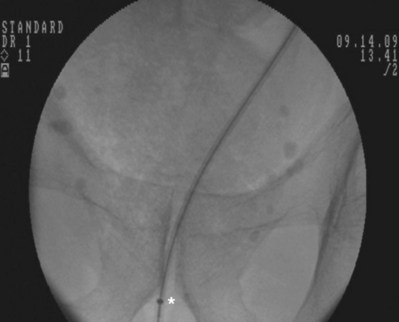

An alternative technique that relies more on fluoroscopic visualization for stent placement and less on cystoscopic visualization is often advantageous when dealing with more challenging stent placements such as impacted ureteral stones or malignant obstruction (Figs. 7-7 through 7-16).

Figure 7–15 While maintaining the tip of the pusher fixed just distally to the inferior border of the pubic symphysis, the 10 portion of the dilator is removed. Asterisk shows the tip of the 10 portion.

Figure 7–16 While maintaining the pusher’s position, the guidewire is removed to form the bladder coil. Then the pusher is removed.

After obtaining bladder access with either a flexible or rigid cystoscope, a floppy-tip guidewire is advanced into the ureteral meatus and coiled in the renal pelvis using fluoroscopy, the cystoscope is then removed and an 8- to 10-Fr coaxial dilator is advanced under fluoroscopy until the 10-Fr sheath is at the urethral meatus. The 8-Fr internal dilator is removed, leaving a conduit (10-Fr outer sheath) through which to advance the stent.

The ureteral stent is then advanced over the guidewire through the 10-Fr sheath by using a pusher with a small fluoroscopically visible metal band at its tip. The metal tip pusher is advanced under fluoroscopic control to the upper border of the pubic symphysis in male patients and lower border in female patients, while stabilizing the position of the lower end of the stent. The 10-Fr sheath and subsequently the guidewire are removed, allowing the stent to curl in the bladder.